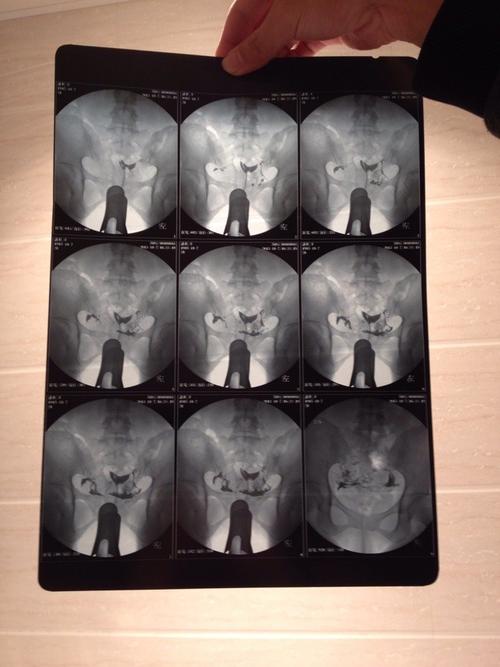

1、输卵管造影是一种传统的检查方式,它使用膀胱截石位,用阴道窥镜的方式对输卵管粘膜进行物理检查,能更直观、快速的了解输卵管粘膜的情况,可检查子宫腔、子宫腔、输卵管、卵巢的恢复情况。而对于有瘢痕组织、坏死组织、积脓、纤维化物,则需要手术治疗。

输卵管造影,顾名思义,是从妇科中通输卵管而使女性的生殖系统恢复正常的生殖功能的一个项目。